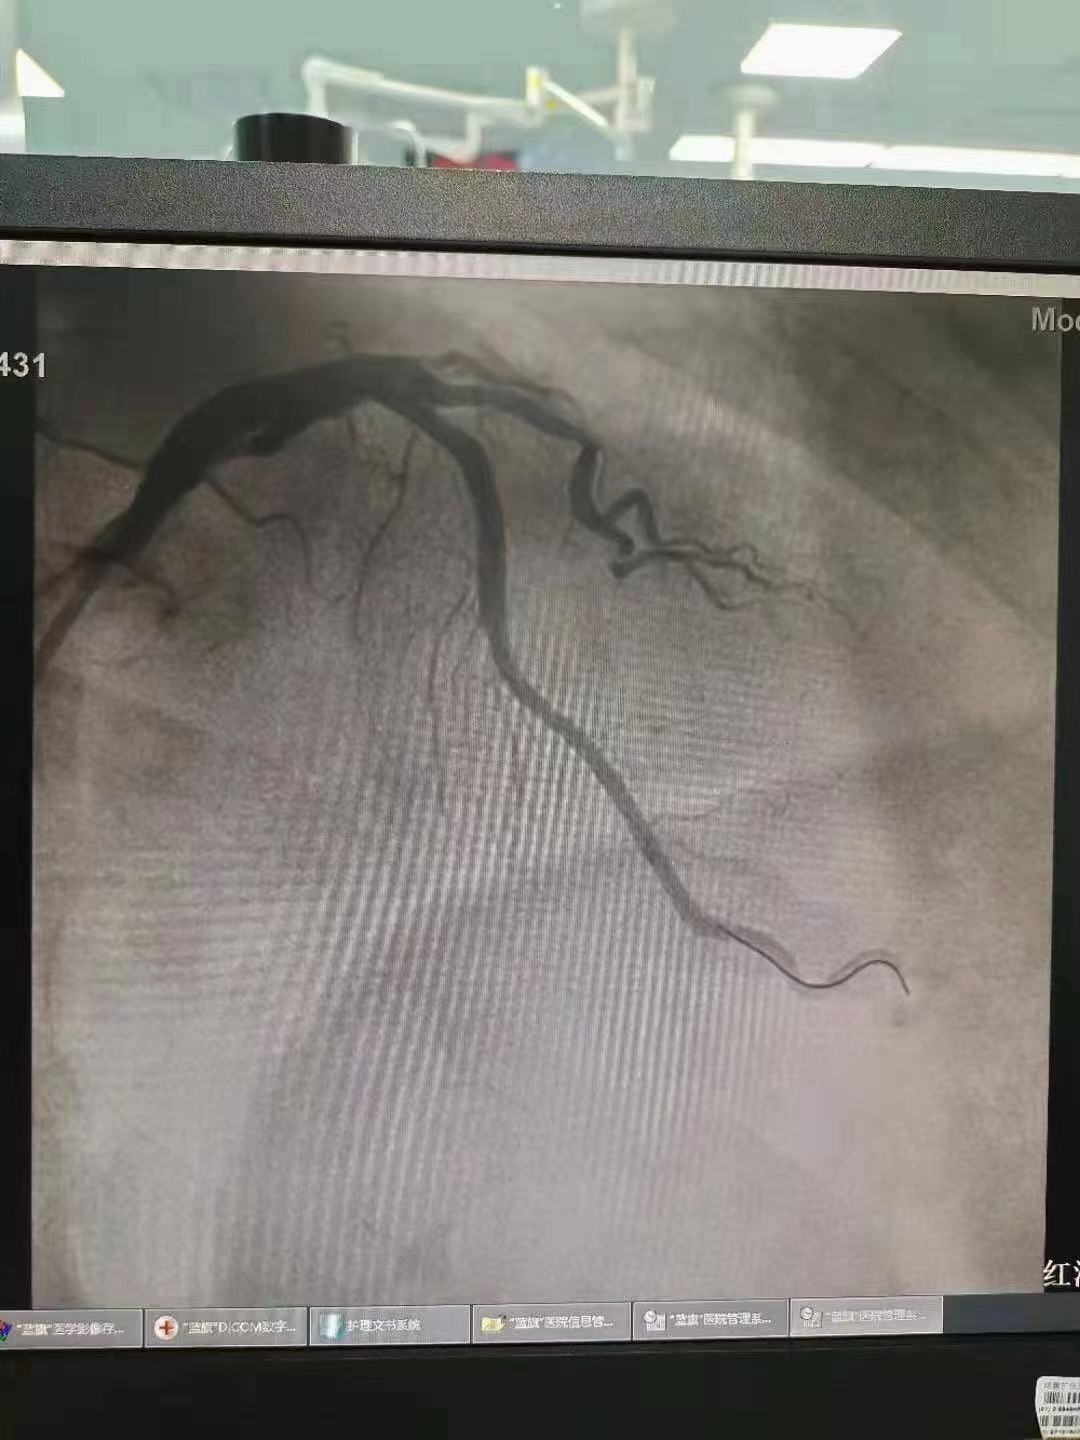

祝賀 云南省滇南中心醫(yī)院  黃銳團隊成功為患者植入3.5~15Xinsorb生物可吸收支架!